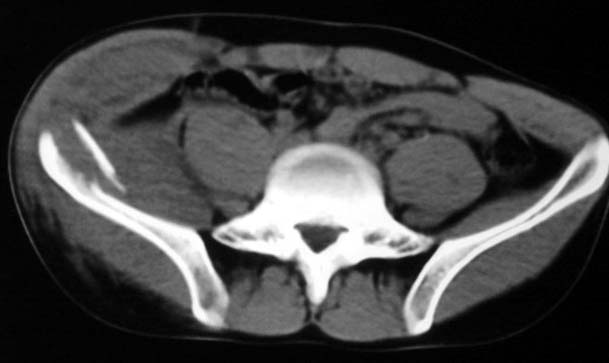

以下是引用守望可可西里在2006-12-13 22:25:00的发言:[br]再明确不过的右侧髂骨骨折,呵呵,这回总不会被忽悠了!

以下是引用liuyue在2006-12-13 23:45:00的发言:[br]右侧髂骨骨折伴局部软组织及腹壁肿胀

以下是引用xiaoniu在2006-12-13 22:22:00的发言:[br]右侧髂前上嵴骨折伴局部腹壁血肿。[br][br][本贴已被 xiaoniu 于 2006-12-13 22:24:13 修改过]